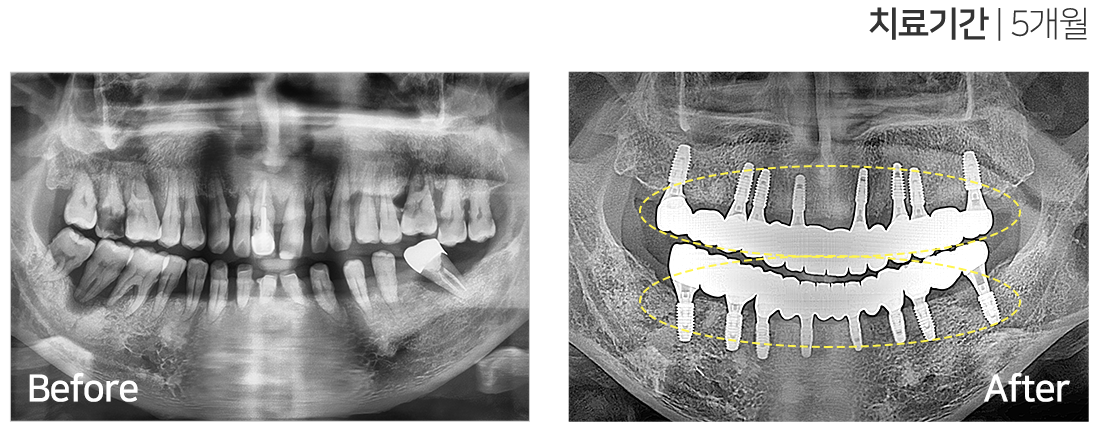

임플란트 시술 사례

IMPLANT TREATMENT CASES

※ 전신질환 및 관리 능력에 따라 임플란트 주위염 등의 부작용이 있을 수 있습니다.